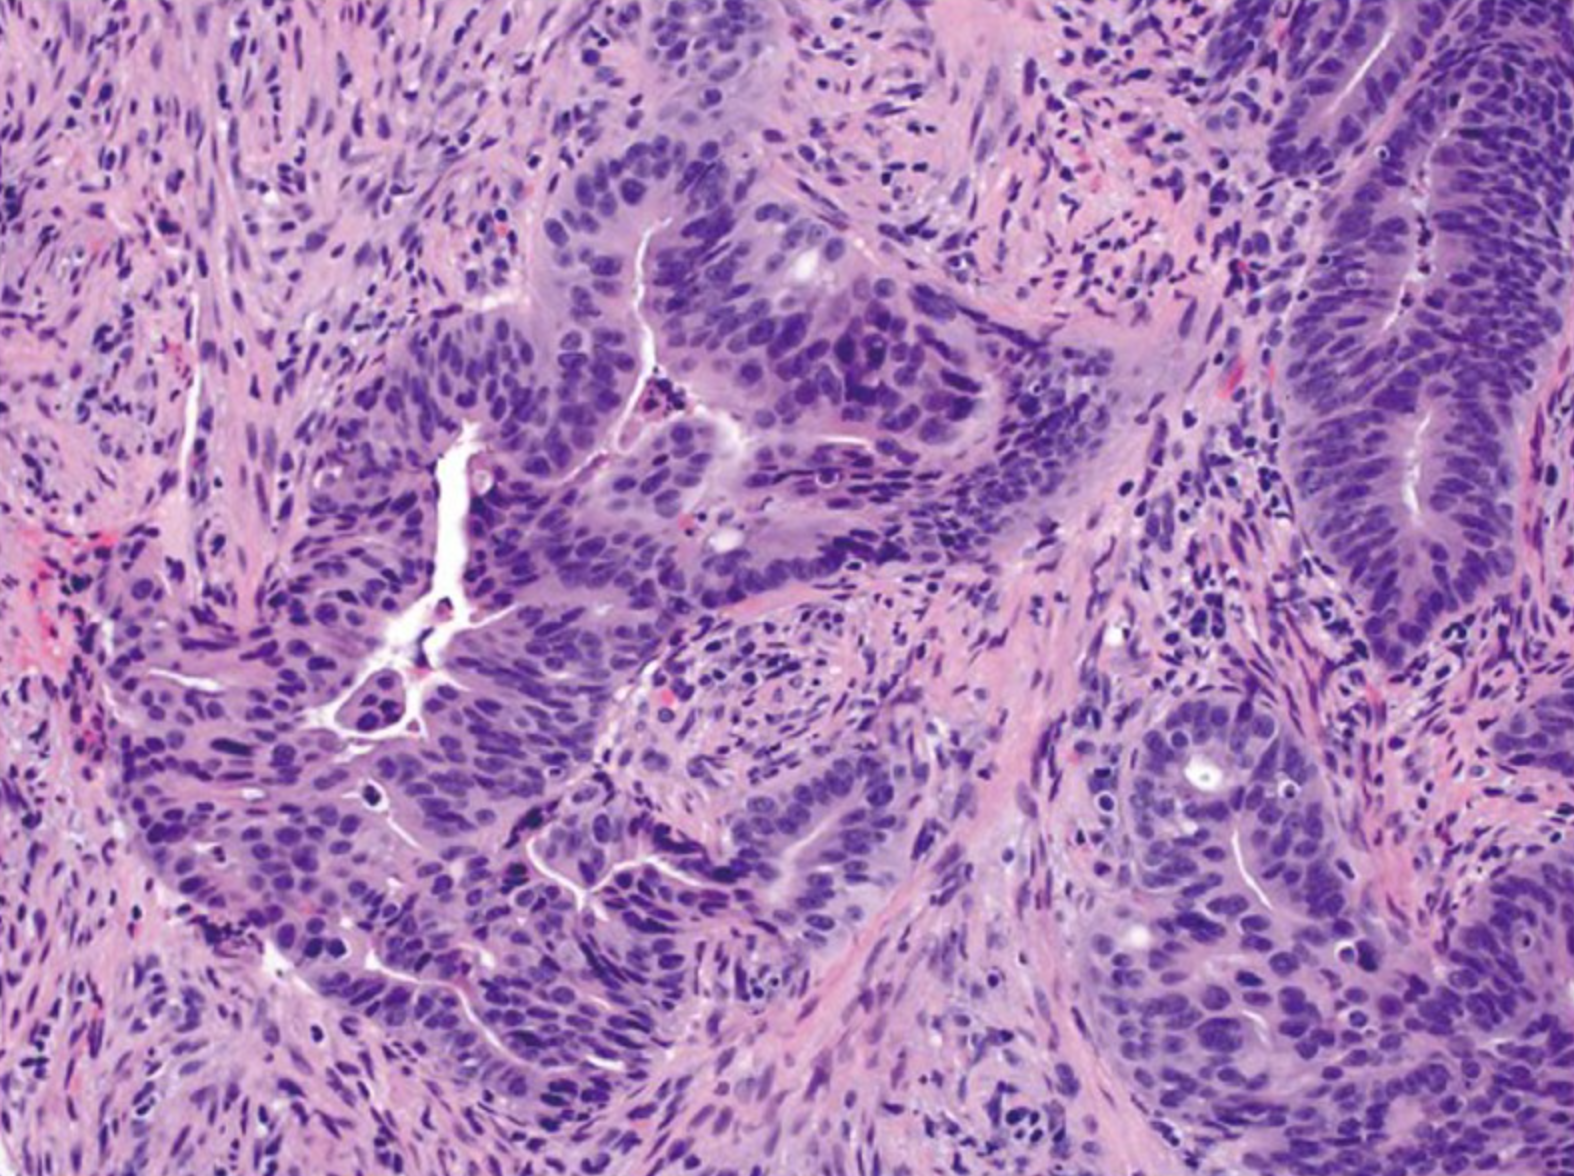

超过90%的结直肠癌是起源于结直肠粘膜上皮细胞的腺癌(adenocarcinoma)。 其他罕见类型的结直肠癌包括神经内分泌细胞癌(neuroendocrine)、鳞状细胞癌(squamous cell)、腺鳞状细胞癌(adenosquamous)、梭形细胞癌(spindle cell)和未分化癌。 常规腺癌以腺状结构为特征,这是肿瘤组织学分级的基础。在高分化腺癌>中,95%的肿瘤是腺形成的。 中分化腺癌显示50-95%的腺体形成。低分化腺癌多为实性,腺体形成率小于50%。 在实践中,大多数结直肠腺癌(约70%)被诊断为中分化(图2)。高分化癌和低分化癌分别占10%和20% [4]。下面将主要介绍几种腺癌的类型。

图2.中等分化腺癌例,在间质间质中可见复杂的腺体结构(放大原图×200) [4]。